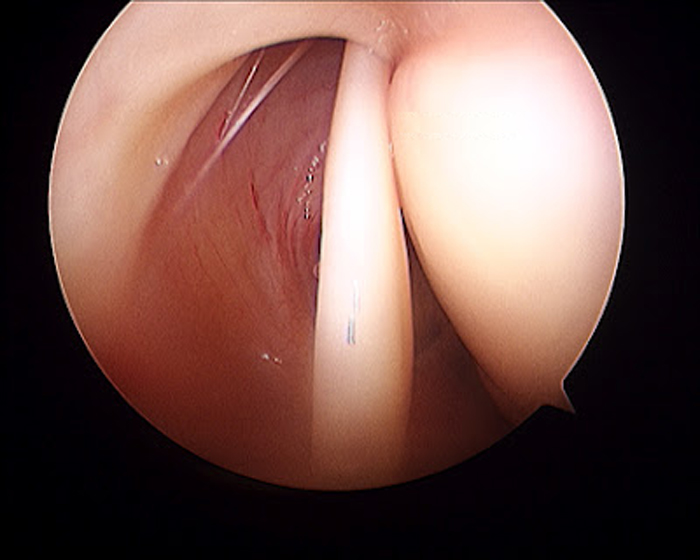

- Lesiones meniscales

- Lesiones cartílago articular